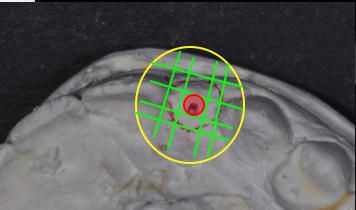

- Obtain diagnostic casts of the edentulous space.

- Measure (with mm calipers) 1.5 mm from each cervical aspect of the adjacent teeth and mark the cast. (Overall space available must be 6.5 mm minimum.)

- Mark the center of the ridge between the adjacent teeth on the cast.

- Duplicate the model.

- Create a diagnostic wax-up for the edentulous space.

- Fabricate a clear acrylic implant placement guide from the wax-up model.

- Place a guide on the mapped model and drill a hole through the guide into the stone at the center mark (a 2.0 mm diameter hole is ideal for the surgeon’s initial twist drill).

- Provide the surgeon with the implant guide prior to implant placement appointment.